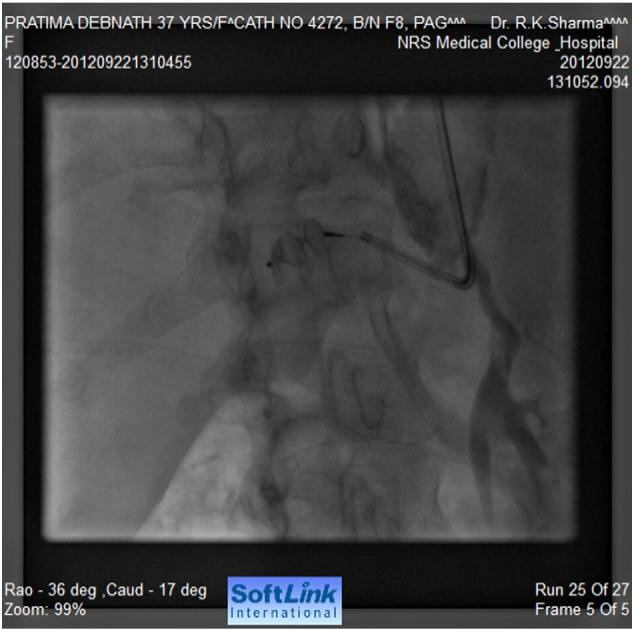

•Here, we are presenting a very rare case of coarctation of abdominal aorta where a transcatheter closure by a vascular plug of the feeding collateral to a large aneurysm has been done. To the best of our knowledge, this mode of therapy has never been described in persons with coarctation of abdominal aorta.•Aneurysms in patients with an abdominal coarctation are not well recognized. This is probably the only case being reported where transcatheter closure of the feeding vessel to the aneurysm has been successfully performed.•In this case, aneurysm was closed by a vascular plug only to prevent sudden rupture and death, and no attempt was made for stenting or dilatation of the atretic segment as the segment was long and no direct connection could be noted between upper and lower segments. The incidence of coarctation of the abdominal aorta is rare and the possibility of aneurysms in coarctation of the abdominal aorta is very rare compared to coarctation of the descending thoracic aorta. Thus, this case is being reported in view of the extreme rarity of the problem.